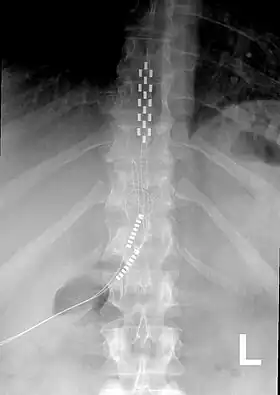

An x-ray showing a spinal cord stimulator implanted into the thoracic spine.

A spinal cord stimulator implanted into the thoracic spine

Neurostimulation for chronic pain is primarily through the use of spinal cord stimulators.[11] These devices deliver electrical stimulation to different areas of the spine based on where they are implanted. Since 2012, Medtronic has produced spinal cord stimulators with accelerometers that can predict the patient's position. The device can be programmed to give additional electrical stimulation if the patient is thought to be in a more painful position.[12]